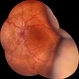

- Ultrawide field fundus photograph of a 62-year-old male with hypotony following blunt ocular trauma